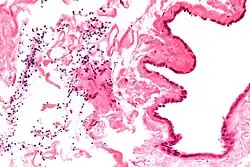

| Spermatocele | |

| Ultrasound of a testicle (grey) and a spermatocele (black). | |